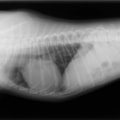

A

B

C

D

A・B:猫の肥大型心筋症による胸水の貯留 正面像と側面像

C:猫の肥大型心筋症による肺水腫 側面像

D:Cの肺水腫治癒後 側面像